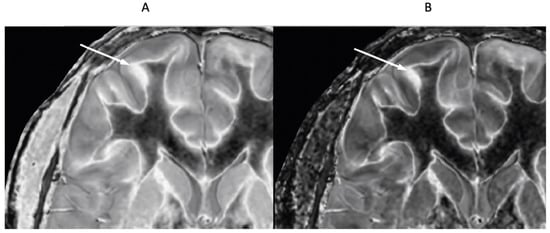

Figure 9 and Figure 10 show a 38-year-old patient with MS in remission (Figure 9A and Figure 10A, left columns) and during a relapse two years and five months later (Figure 9B and Figure 10B, right columns) imaged with the same narrow mD dSIR sequence. Figure 9 shows three positionally matched lower levels in the brain and Figure 10 shows two positionally matched higher levels in the brain. White matter shows a generally low signal during remission (whiteout sign grade 1–2) (Figure 9A and Figure 10A), and a high signal (whiteout sign grade 4–5) during the relapse (Figure 9B and Figure 10B). The multiple levels within the brain show the wide distribution of the high grade whiteout sign in the cerebellar and cerebral hemispheres, as well as in the brainstem. No evidence of a whiteout sign was seen on the corresponding T2-FLAIR images.

Figure 9.

Thirty-eight-year-old female patient with MS in remission (A, left column) and during a relapse (B, right column) two years and five months later. Matching narrow mD dSIR images at three lower levels in the brain. In remission (left column), there are bilateral symmetrical areas of low signal in the white matter of the cerebellar and cerebral hemispheres. The corresponding areas show increased signal during the relapse (right column) consistent with a grade 4–5 (out of 5) whiteout sign. No evidence of a whiteout sign was seen on the T2-FLAIR images.

Figure 10.

Thirty-eight-year-old female patient with MS in remission (A, left column) and during a relapse (B, right column) two years and five months later (same case as in Figure 9). Matching narrow mD dSIR images at two higher levels in the brain. In remission, white matter shows a low signal (left column). This is increased during the relapse in a bilateral symmetrical distribution consistent with a grade 4–5 (out of 5) whiteout sign (right column). No evidence of a whiteout sign was seen on the T2-FLAIR images.